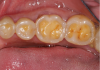

Fig 6. Eroded and worn occlusal surfaces with hollowed out areas.

Figure 6

Concavities on the lingual surfaces of maxillary incisors (Figure 5) or occlusal surfaces of premolars and molars (Figure 6) with hollowed areas are signs of dental erosion that may be combined with attrition. Gastric acid is the most common cause of erosion on the lingual aspects of teeth. The most frequent etiology of gastric acid attack is the clinical diagnosis of GERD.13 Patients with anorexia nervosa and bulimia nervosa exhibit higher incidences of dental erosion.29 In Figure 7, a schematic drawing of an upper incisor demonstrates the sequence of loss of dentin and enamel on the lingual/palatal aspect. The direct contact of acid on the tooth structure is the main mechanism as the inorganic material dissolves, leading to a loss of surface hardness.13

The BEWE is a scoring system that evaluates the most severely affected surface in each sextant, recording one of the four-level scores as follows30: 0 = no erosive tooth wear (Figure 8); 1 = initial loss of surface texture (Figure 9); 2 = distinct defect, hard-tissue loss <50% of surface area (Figure 10); 3 = hard-tissue loss ≥50% of surface area (Figure 11). (Scores 2 and 3 often involve dentin.) After all sextants are assessed, the sum of scores provides the risk level of each patient and may help guide the design of a professional management program for the patient.

Fig 10. BEWE scoring system: score 0 = no erosive tooth wear (Fig 8); score 1 = initial loss of surface texture (Fig 9); score 2 = distinct defect, hard-tissue loss <50% of surface area (Fig 10); score 3 = hard-tissue loss ≥50% of surface area (Fig 11)

Figure 10